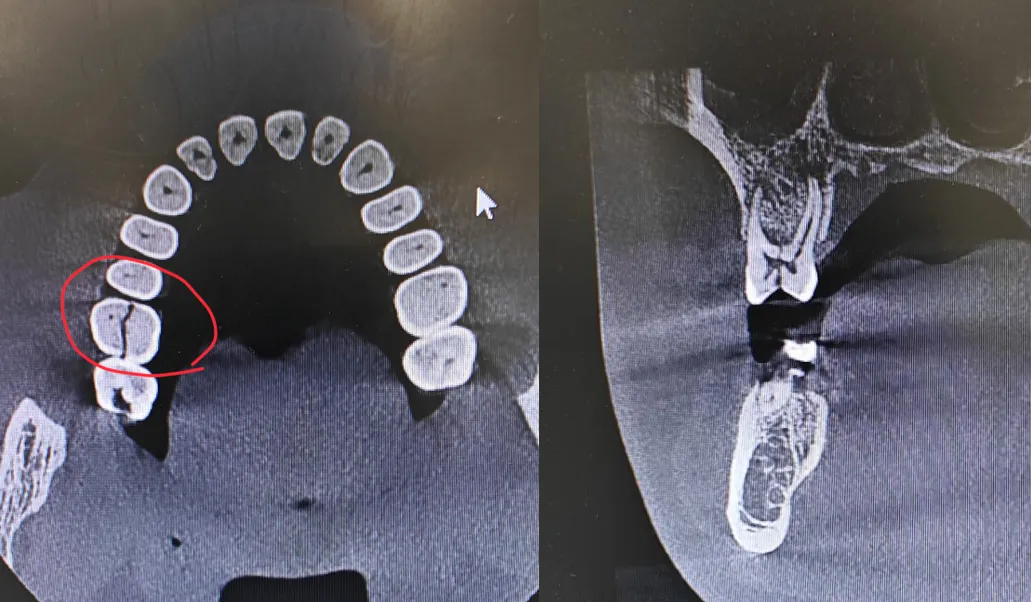

今年920爱牙日主题是“减糖控体重,护牙促健康”,控糖并非小事情,让我们一起爱护宝宝们的牙齿健康~儿童口腔疾病位于儿童常见疾病的前列,它不仅会影响孩子的口腔健康,更会对儿童的生长发育、学习生活造成较大的负面影响。WHO及许多国家均已将儿童列为口腔疾病防治的重点人…